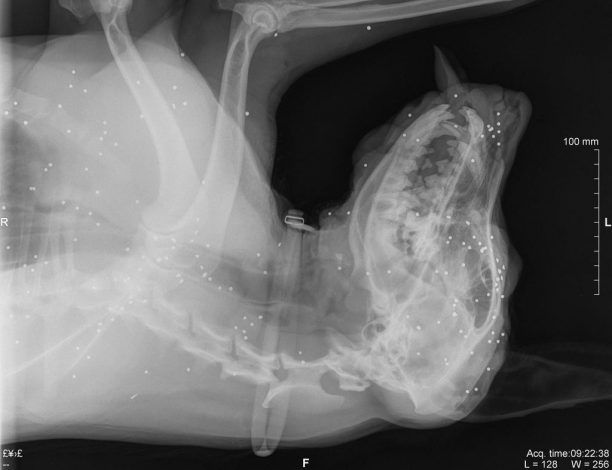

Ευθανασία αναγκάστηκε να κάνει η Barbara Exner στον θηλυκό σκύλο της καθώς το ζώο, που προπορεύτηκε κατά τη διάρκεια της βόλτας - αφού η κηδεμόνας του το είχε χωρίς λουρί - τελικά εντοπίστηκε πυροβολημένο στο κεφάλι με καραμπίνα στο Δρέπανο Αργολίδας κοντά στο νεκροταφείο της περιοχής στις 3 Οκτωβρίου.

Το ζώο μεταφέρθηκε από την ιδιοκτήτρια του και τον σύζυγο της Hans J.F. Krause στο κτηνιατρείο της Ελένης Σταματίου και εκεί διαπιστώθηκε ότι το σκυλί είχε χάσει οριστικά την όραση του και δεν μπορούσε να κουνήσει τα άκρα, έτσι του έγινε ευθανασία, ώστε να μην υποφέρει περαιτέρω. Σύμφωνα με την καταγγέλουσα το Α.Τ. Ναυπλίου στο οποίο πήγε για να κάνει καταγγελία δεν έδειξε ιδιαίτερο ενδιαφέρον για την υπόθεση...